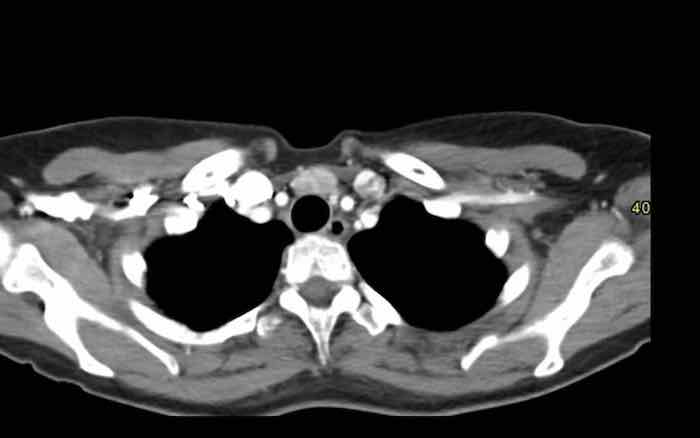

Các hình ảnh này của một nam giới 19 tuổi, được chụp CT để loại trừ thuyên tắc phổi.

Phát hiện tình cờ một khối ở khoang trước mạch máu.

Chẩn đoán có khả năng nhất là tăng sản tuyến ức và MRI được thực hiện để phân biệt thêm khối này.

Trên hình ảnh chuỗi xung T2W, tổn thương có tín hiệu tăng nhẹ.

Trên hình ảnh pha đối (out-of-phase), không có sự sụt giảm tín hiệu đáng kể.

SII nhỏ hơn 9%.

Do bệnh nhân không có bất kỳ triệu chứng nào, đặc biệt không có các triệu chứng có thể liên quan đến u lympho, và vì u tuyến ức (thymoma) là một khối u hiếm gặp, quyết định được đưa ra là theo dõi sau sáu tháng.

Tại thời điểm theo dõi sáu tháng, tuyến ức có hình ảnh bình thường.

Kết luận được đưa ra là đây là tăng sản tuyến ức hoặc mô tuyến ức tồn dư kích thước lớn, đã thoái triển trong vòng sáu tháng.